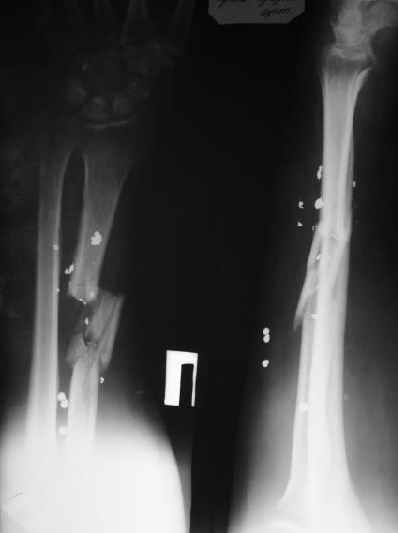

Мужчина 36 лет 5 мес. назад получил дробовое ранение правого предплечья с переломом лучевой кости, повреждением лучевой артерии и срединного нерва.

В больнице по месту жительства обрабатывали рану,сделали несвободную кожную пластику, синтезировали спицей интрамедуллярно, потом убрали. Свищей нет. Линейный рубец по лучевой стороне, приживший лоскут по ладонной (см. картинку).Cращение не произошло (см. снимок).Нейрохирурги что-то надеются сделать, но условием ставят стабилизацию лучевой кости.Какой вариант тут предпочесть? Представляется оптимальным аппаратом дозированно подправить длину и ось, и закрыто ввести интрамедуллярный стержень. Не особо даже рассчитывая на сращение, а только восстановить форму и длину кости, и создать "эндопротез диафиза". Или подумать про какие-то другие варианты?A male 36 years old 5 month ago sustained a gun-shot wound with the radial fracture and lesion of a.radialis and n.medianus. Debridement was performed at the initial hospital, full-thickness skin grafting and intramedullary fixation of the radius by a small wire, which later was removed. No sinuses and signs of infection to date. A linear scar on the radial side and the healed flap (see image). Healing was not reached (see x-rays).Neurosurgeons hope to do something with the peripheral nerves but only in case of stabilization of the radius.Which treatment modality should be preferred? I would perform gradual alignment with the Ilizarov, and perform secondary closed nailing. Even not to expect to reach union, just to restore length andalignment with the "shaft endoprosthesis". Or it is worth to think about other options?

Вариант: После устранения укорочения освежить место перелома (т.к., судя по рентгенограмме, имеется выраженный остеосклероз дистального отломка, закрыт костно-мозговой канал), и провести свободную костную пластику трансплантатом из гребня подвздошной кости.

ВНУТРИКОСТНЫЙ И НАКОСТНЫЙ ОСТЕОСИНТЕЗ проводить НЕРАЦИОНАЛЬНО, т.к. имеется выраженный остесклероз в зоне несращения как следствие нарушенного кровоснабжения.